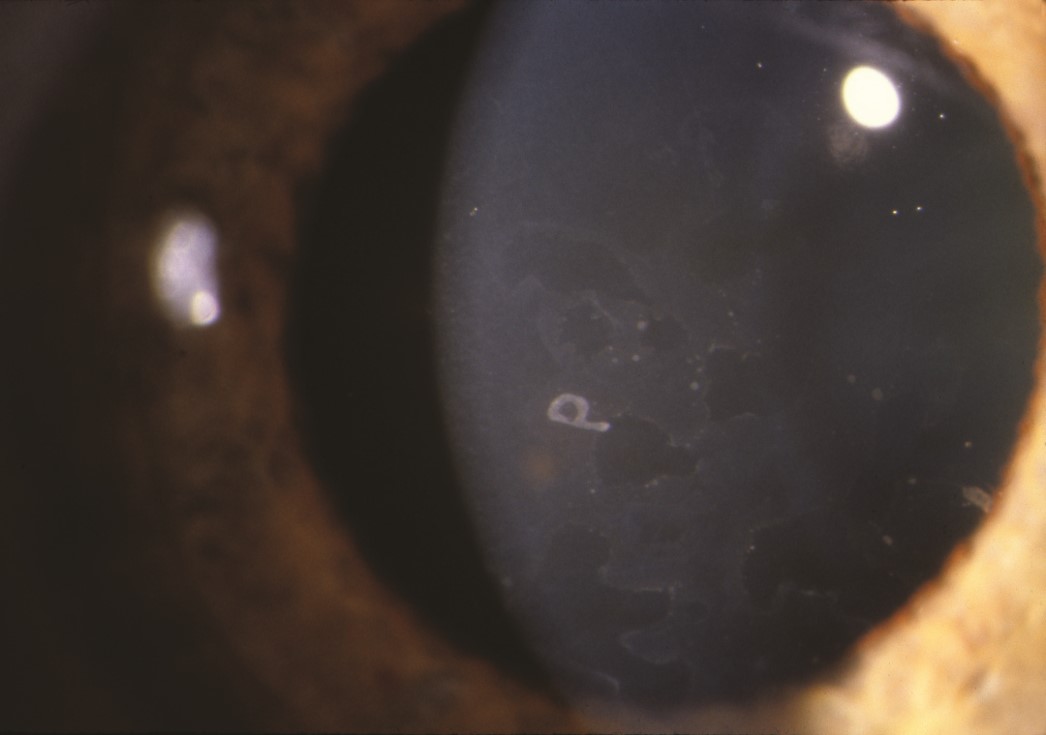

Corneal epithelial basement membrane dystrophy. This common disorder disrupts the normally smooth optical surface of the cornea/tear film with ridges of epithelial irregularity. This may have a geographic appearance like a map, appear as dots on the surface of the cornea, or have irregular parallel ridges that resemble a fingerprint (hence, the alternative descriptive name: map, dot, fingerprint dystrophy). The map-like appearance and dots are evident on this clinical photograph of the cornea of a patient who presented with unexplained intermittent blurred vision.

Source: Martin TJ, Corbett JJ. Practical Neuroophthalmology; 2013.